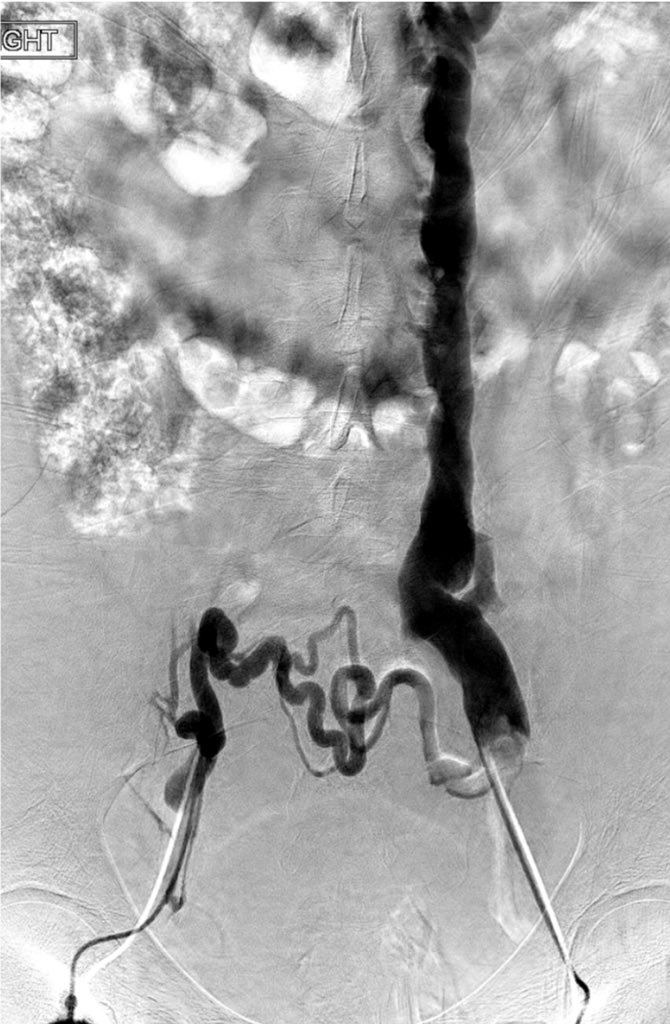

@ChengaziMD @t_intheleadcoat @SDhandMD @drochohan @kmadass @JayMathewsMD @CHICKVIR @Dr_Sudi @DrJayMohan @hkdamonster @SyedYNaqvi1 Nice save with minimal XR, a little IVUS as well? Lucky to have your expertise. I’ve also been preferring IJ when possible